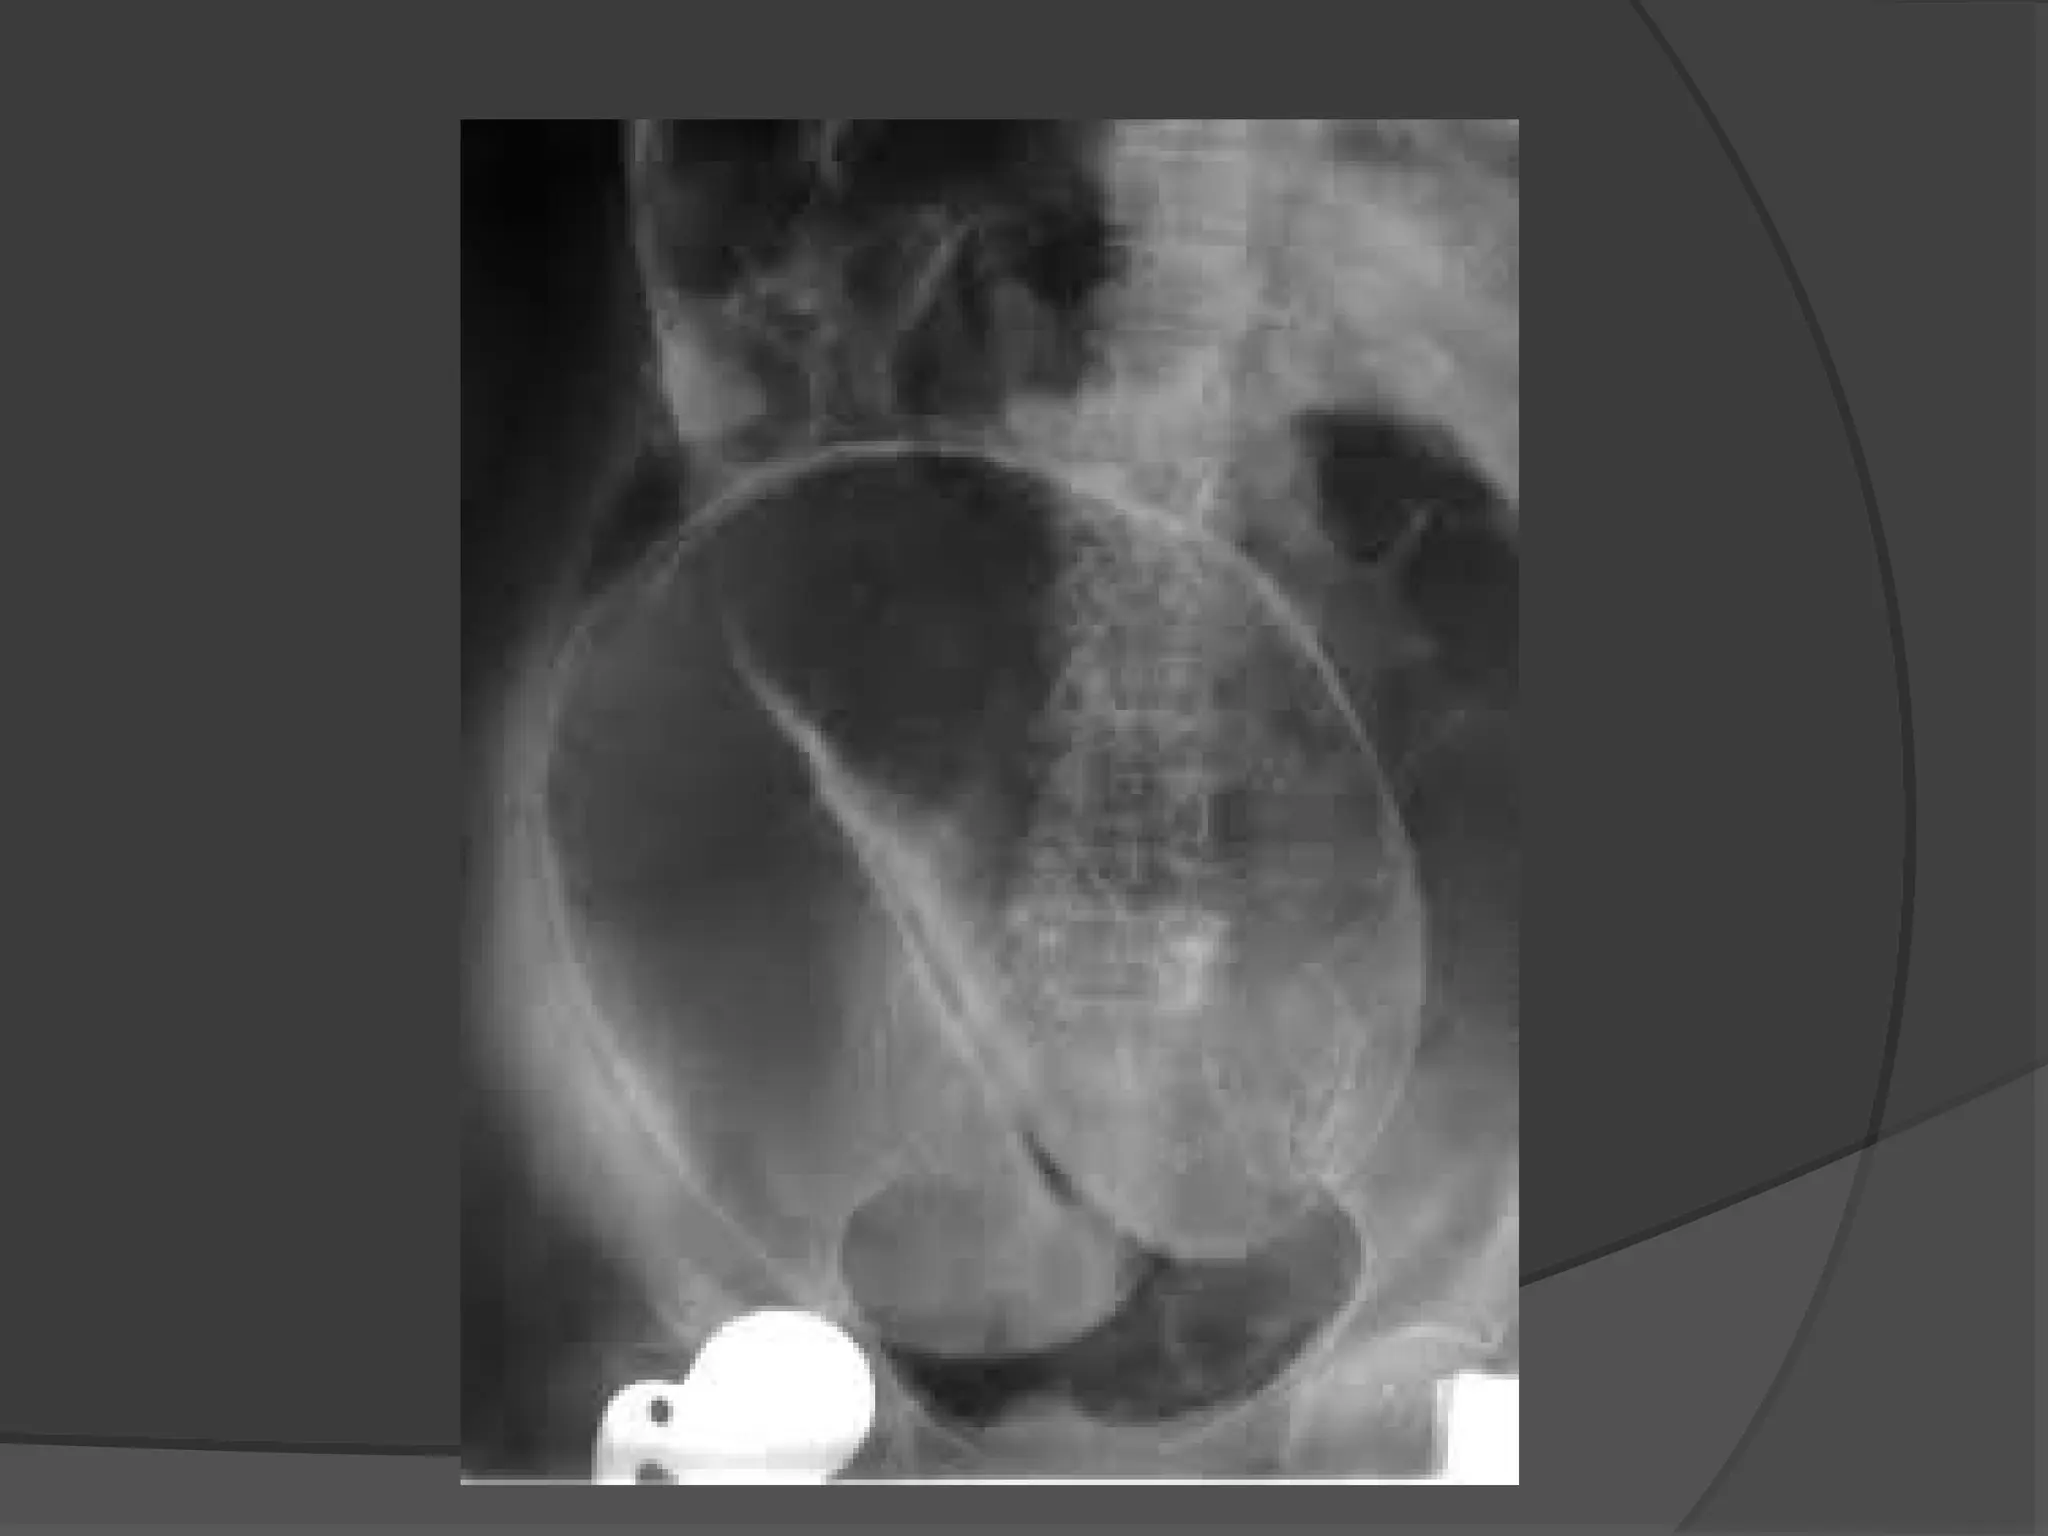

 Volvulus of the sigmoid colon -a grossly dilated

loop of colon, with or without visible haustrae

which arises from the pelvis and extends

obliquely across the spine to the upper abdomen.

4) Sigmoid Volvulus

 An anticlockwise twist .

 Most Common spontaneous Volvulus in

Adults.

 Chronic constipation is a predisposing

factor.

Sigmoid Volvulus

90

This is uncommon in Europe and the United States,

but more common in Eastern Europe and Africa.

it is the most common cause of large bowel

obstruction in the Black African population.

Rotation nearly always occurs in the anticlockwise

direction.